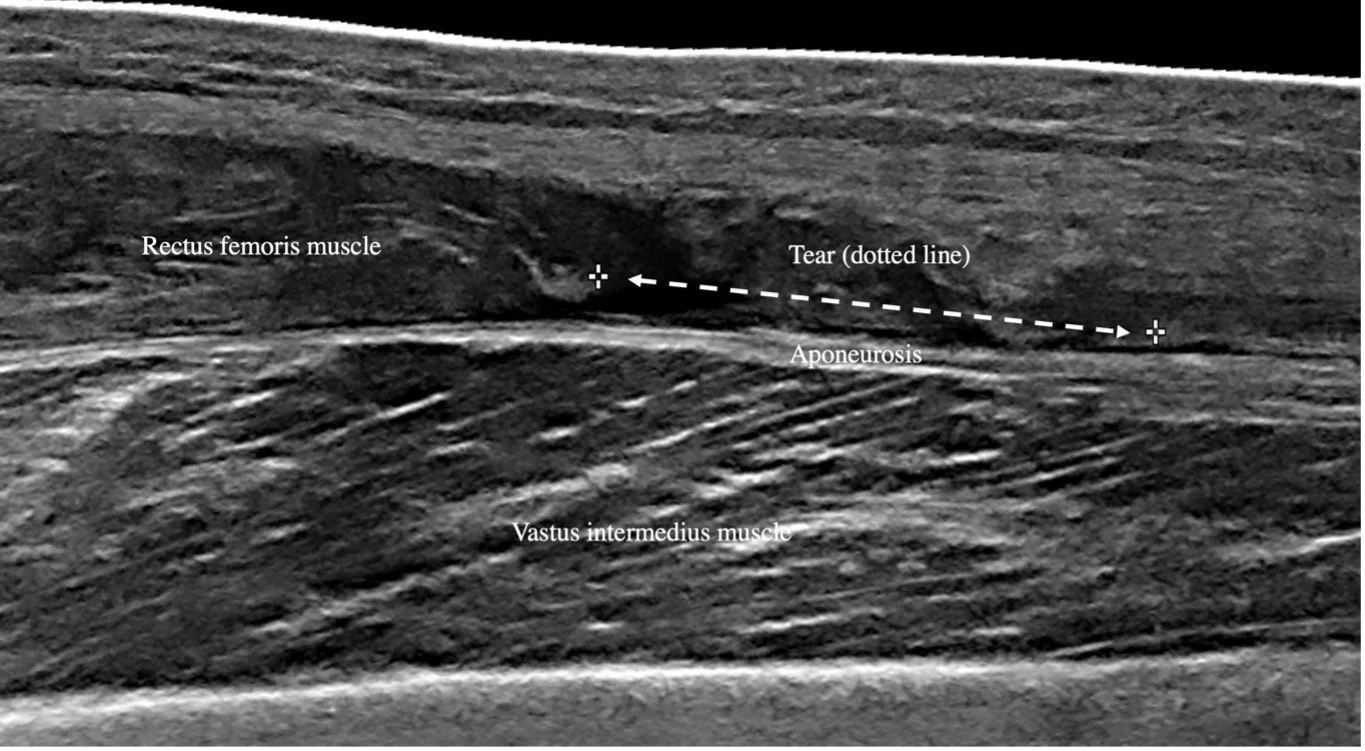

In de foto hieronder zien we de beenspieren vanaf de zijkant. Wat opvalt is dat ze links in de groene spier allemaal lijntjes hebben getekend. Deze lijntjes zien we ook terugkomen als we met ultrasound een beeld van een spier proberen te krijgen. (En de vezels zie je misschein ook als je een biefstuk bakt, wat immers ook een stuk spier is!)

Als we dieper inzoomen op de spier worden de de lijnen nog duidelijker zichtbaar. Hieronder is weer het been, maar nu van een zittende man, het been is nu horizontaal.